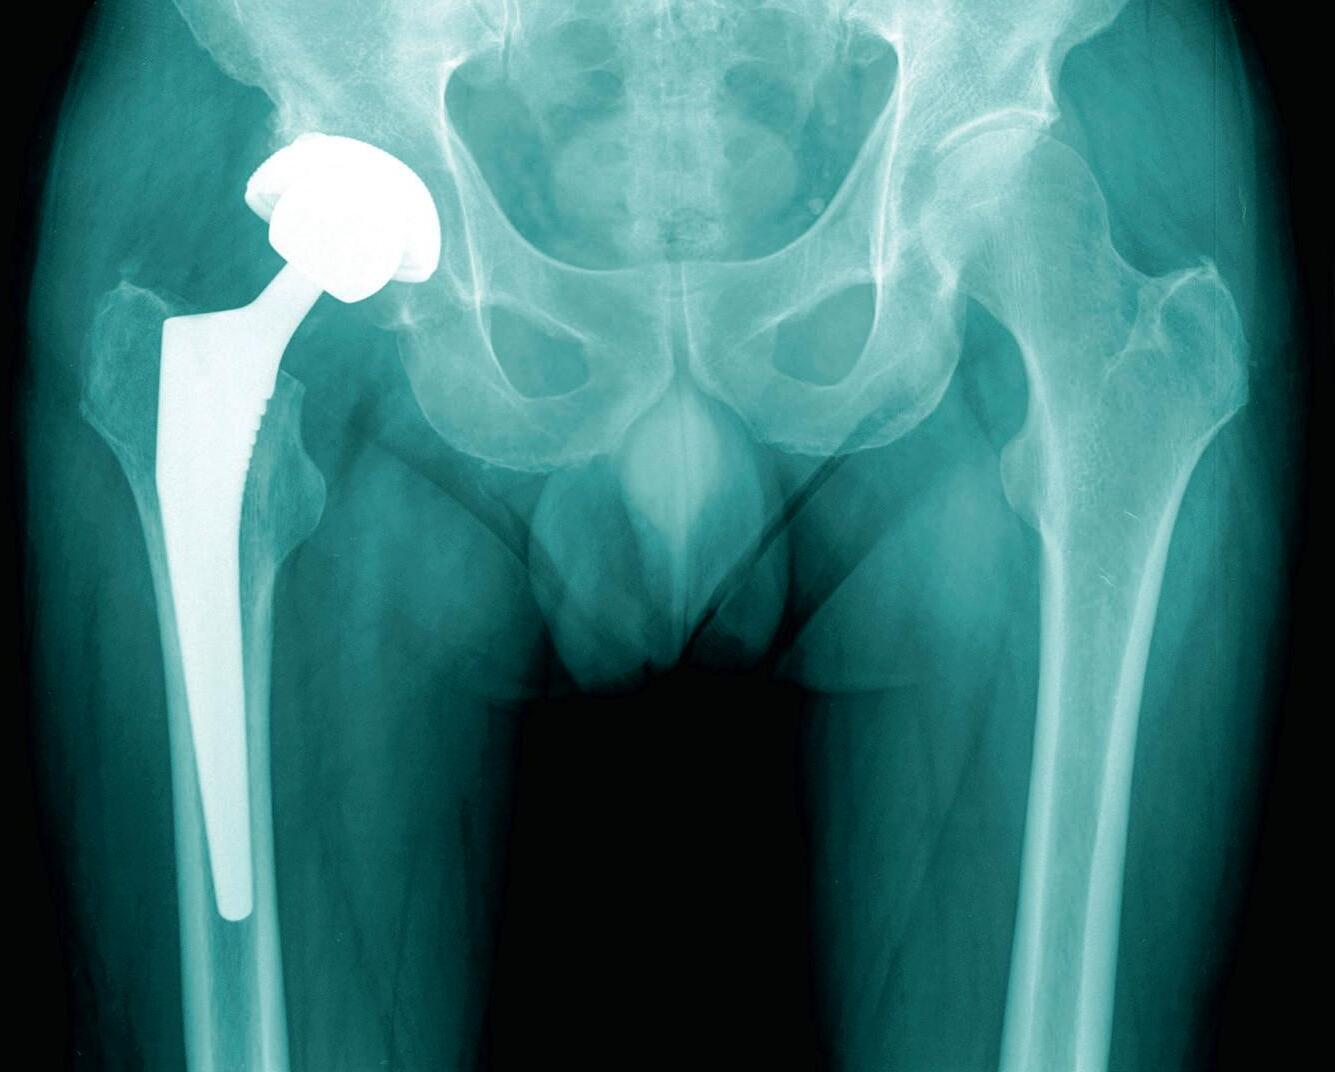

104 Hip, Hop, Don’t Stop

Is hip pain slowing you down? Replacing a painful joint is becoming faster and easier as medical technology improves